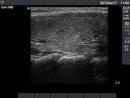

First examination (first row):

Ultrasonography: Both lobes were enlarged, moderately hypoechogenic, inhomogeneous and displayed increased vascularization.

Diagnosis: Graves' hyperthyroidism.